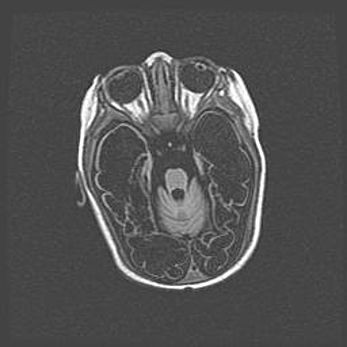

Неполная лизэнцефалия (пахигирия). Открытая гидроцефалия.

Возраст: 17 дней

Вес: 3110 г

Пол: мужской

Окружность головы: 33,5 см

Срок гестации: 35-36 недель

Лизэнцефалия—недоразвитие корковой пластинки и мозговых извилин в результате нарушения миграции нейронов коры. Поверхность мозговых полушарий гладкая. Микроскопически выявляется отсутствие нормальных слоев коры и скопление групп нейронов в подкорковом белом веществе.

Пахигирия—уменьшение числа вторичных извилин. В пораженном полушарии нервные клетки образуют толстый недифференцированный слой с неправильно расположенными нервными волокнами и группами гетеротопных клеток. Нервные клетки незрелые. Белое вещество истончено. При этом нередко аномально развит корково-спинномозговой путь.